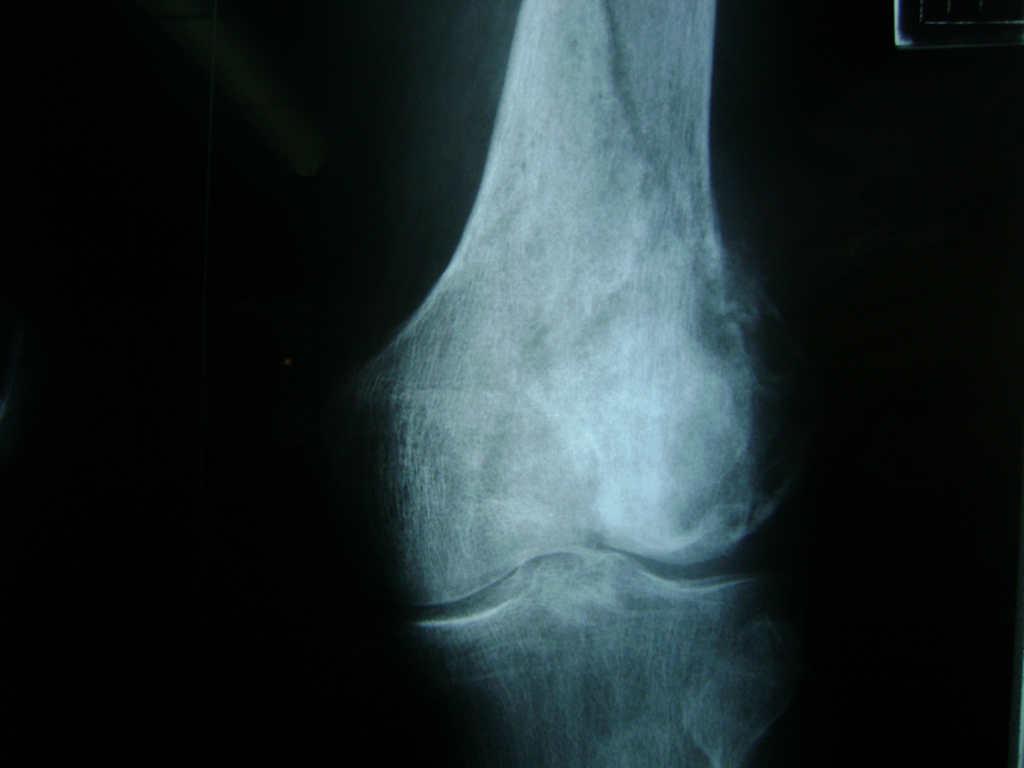

La artroscopia de rodilla es un cirugía en el cual la estructura interna de la articulación es examinada ya sea para realizar un diagnostico o para realizar un tratamiento, este procedimiento se realiza utilizando un instrumento parecido a un pequeño tubo llamado artroscopio.

La artroscopia se popularizo en 1960 y hoy en día es muy común en todo el mundo. Típicamente, es realizada por cirujanos ortopédicos de manera ambulatoria. Cuando se realiza de manera ambulatoria los pacientes pueden regresar a casa después de la operación, no se requiere quedarse en hospital.